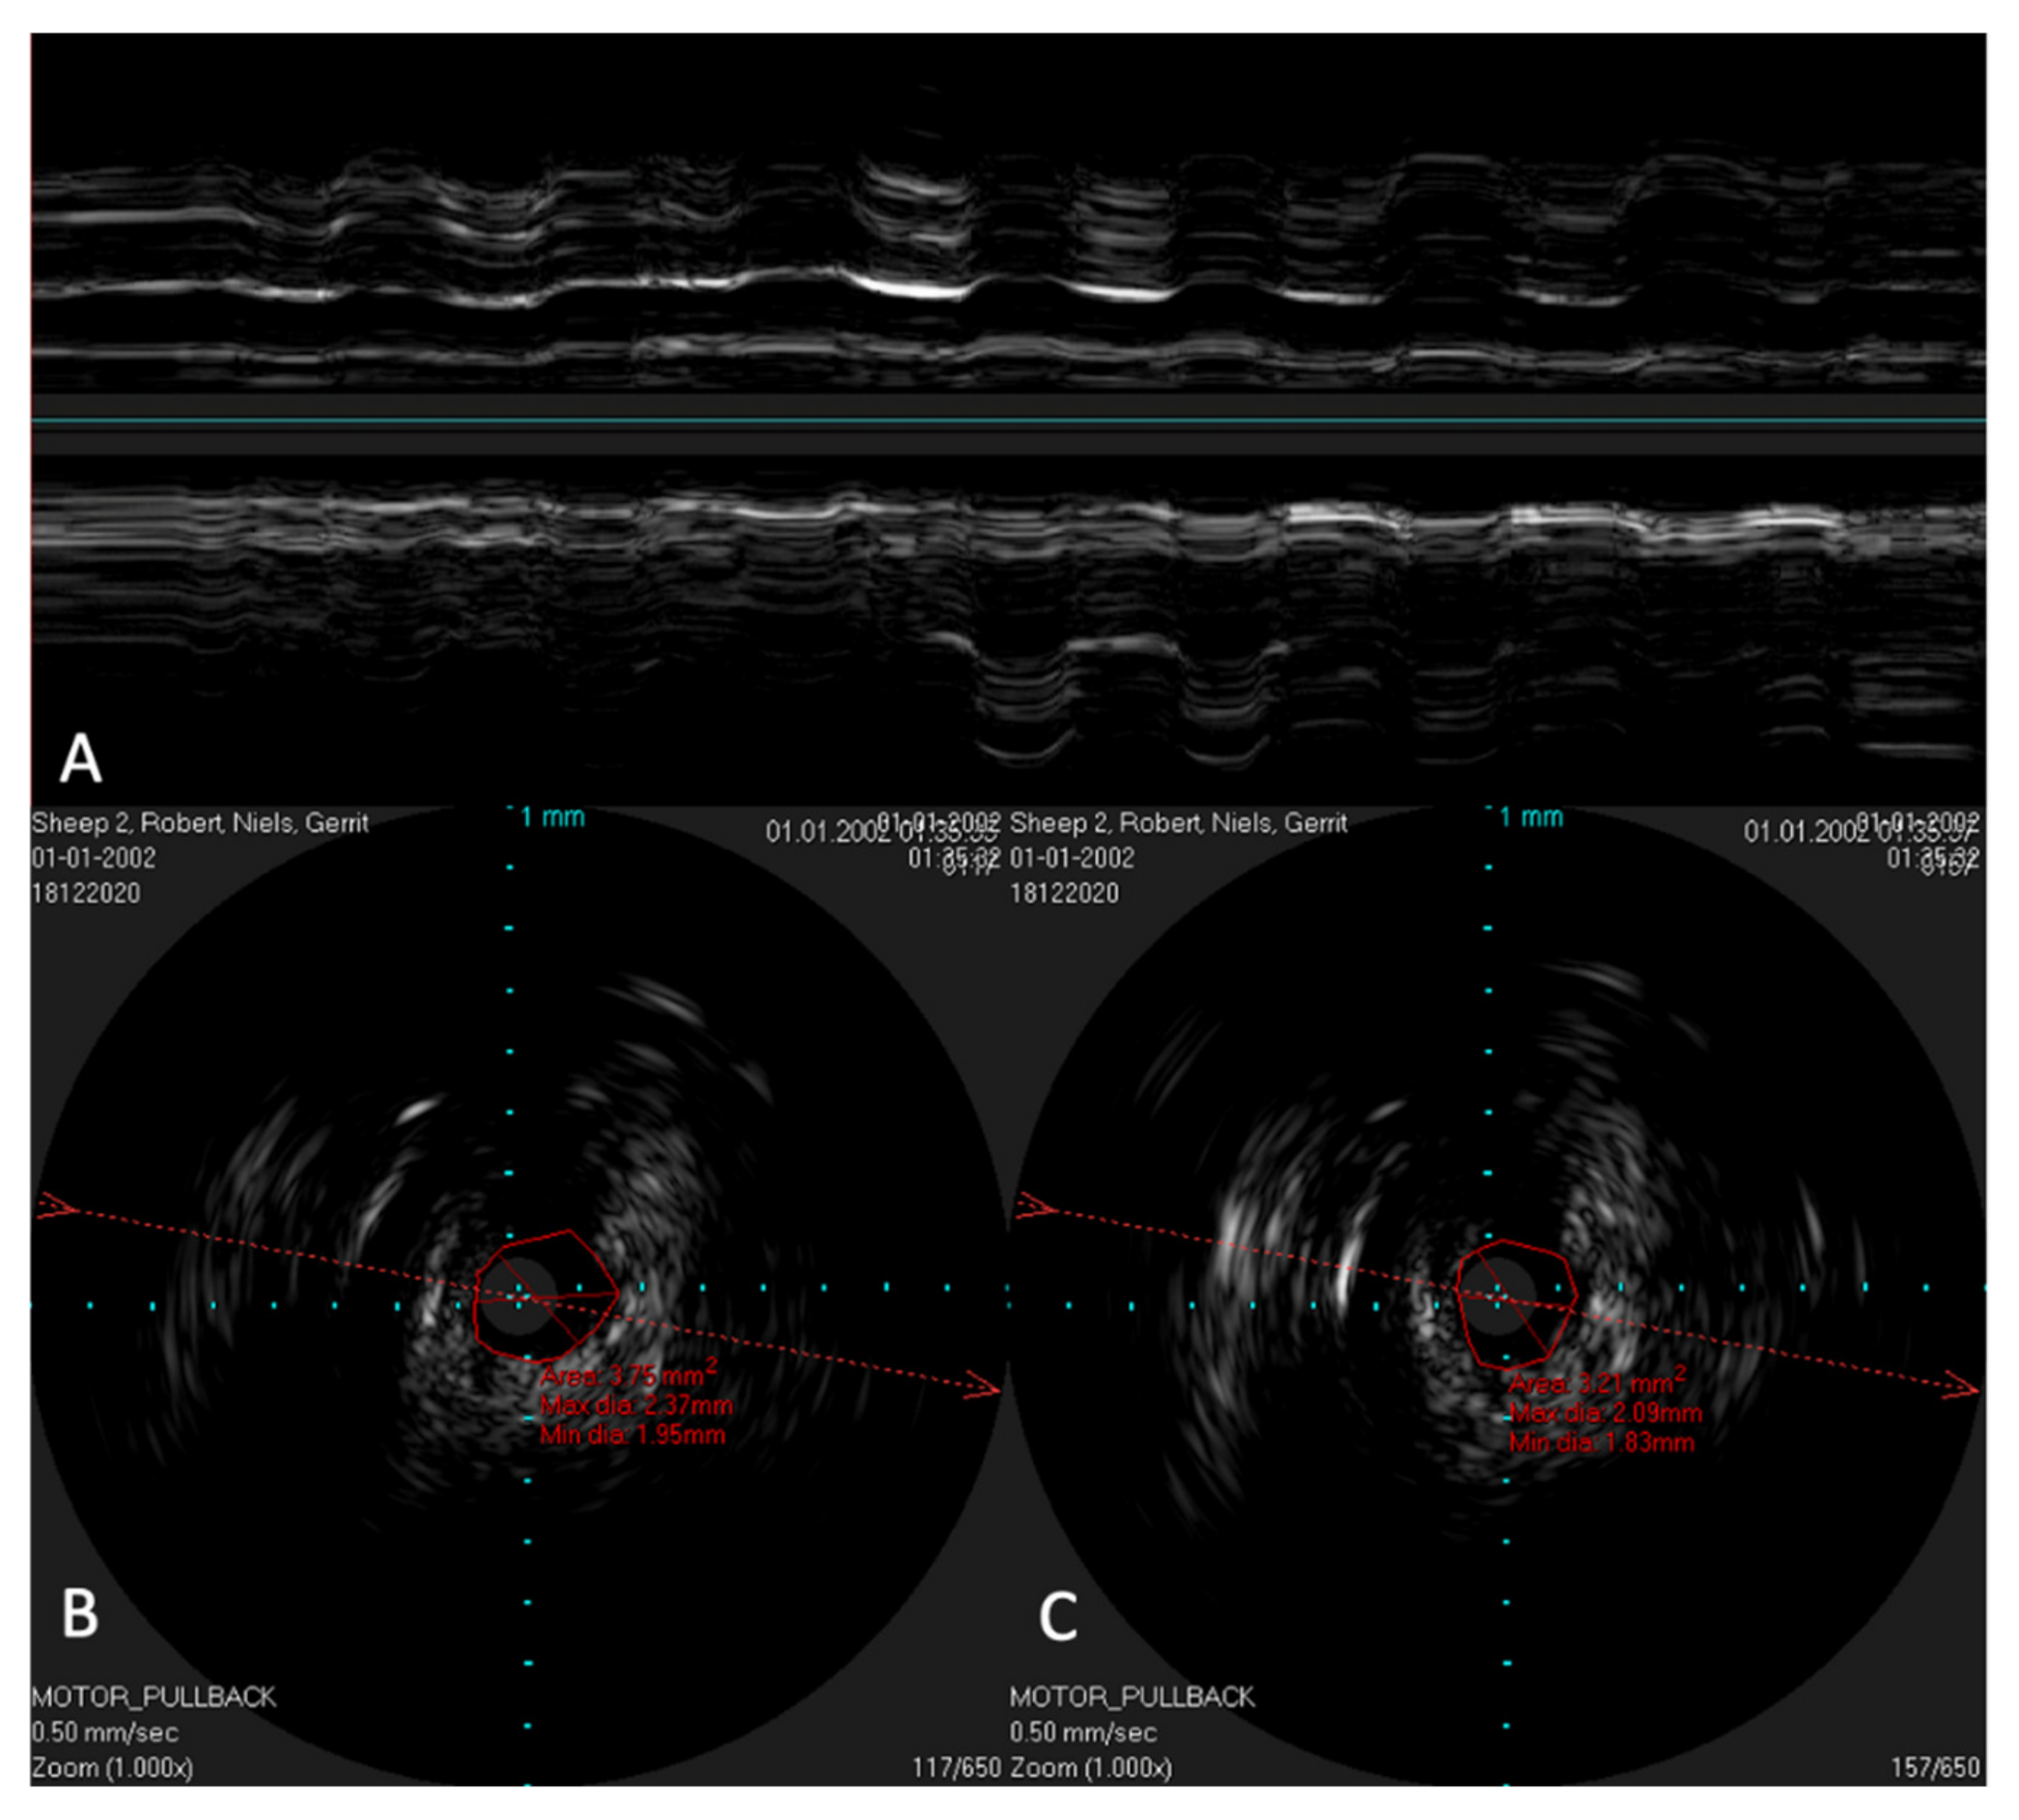

In order to possibly investigate the function of the ET, the lower jaw was moved manually during scans with a stationary IVUS catheter in the ET. An extension of the lumen and, thus, a size change of the lumen could be visualized (Figure 9) in the time-based longitudinal view. With the lower jaw closed, a lumen size of 3.21 mm2 was measured. The probe itself had a size of 1.33 mm2. With the mandible open, this lumen increased to 3.75 mm2. In the longitudinal view, this repetitive size change was clearly visible as waves.

Figure 9. Ultrasound image of the ET with a stationary IVUS probe. During the scan, the lower jaw was repeatedly moved manually, thus opening and closing the sheep’s mouth. Image (A) shows the ET over time. The lumen changes and movements of the surrounding structures can be seen as waves. Part (B) shows the cross-section of the tube with the mouth open, with an approximate tube lumen of 3.75 mm2, where the probe has an area of 1.33 mm2. Part (C) shows the same area with the jaws closed, where the tube lumen has decreased to 3.21 mm2.